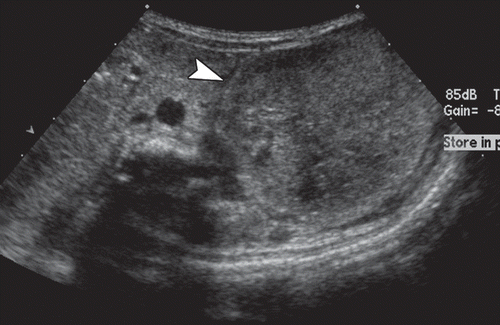

Newborn with a hypoechoic lesion on ultrasound

MESOBLASTIC NEPHROMA.

Wilms like tumor, but <1 month old.

Solid renal tumor of infancy. Fetal hamartoma. Most common renal tumor in the first month of life.Involves renal sinus.